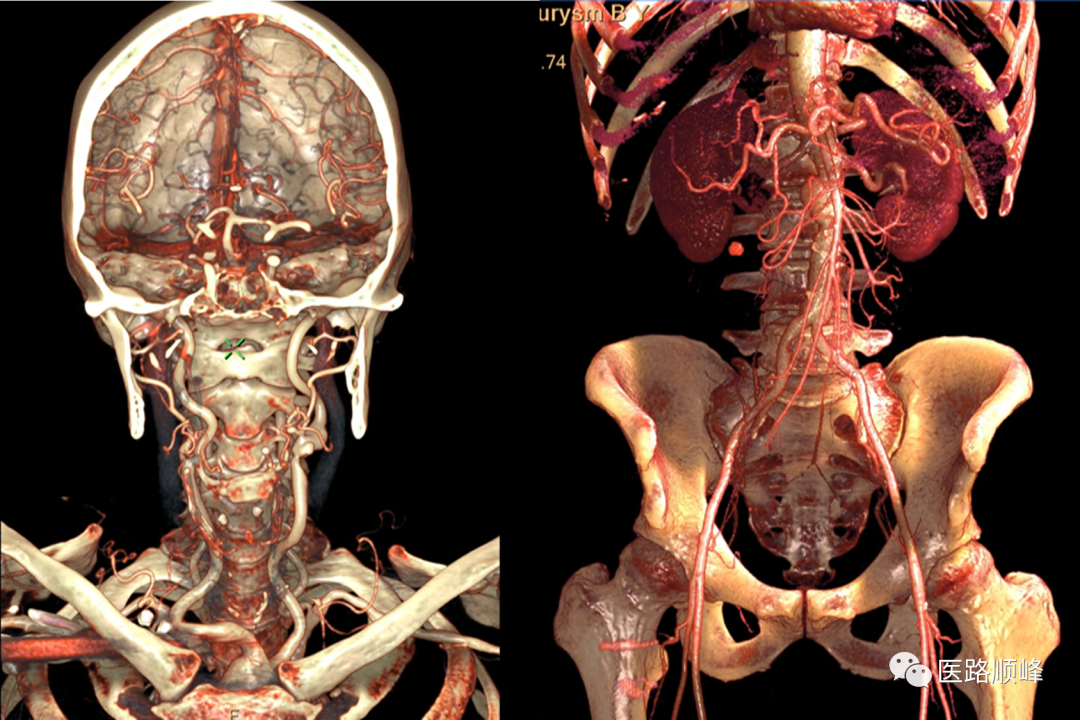

• 全身血管CTA精准成像

满足心脏、大血管、大范围扫描需求,临床综合能力强。

ct为什么需要预热机器Computed Tomography专栏:Incisive CT 球管预热_https://www.jmylbn.com_新闻资讯_第18张